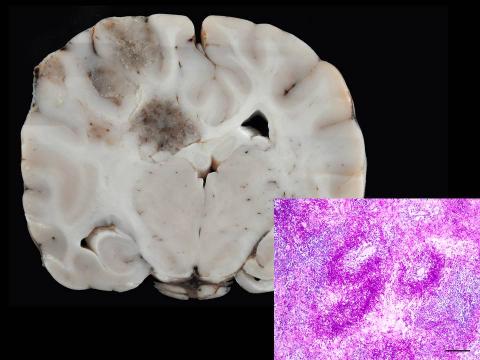

Autopsy findings: In the right, rostral part of the cerebrum, 5 blurred, gray-beige, cheesy, partly coalescing lesions with a diameter of up to 0.9 cm were visible. Similar changes with variable degrees of expression were found in the mass of the left forelimb, several lymph nodes, myocardium, pancreas, kidneys, adrenal glands, and thyroid gland.

Histopathological findings: Multifocal identification of abundant amounts of inflammatory cells consisting of macrophages (some epithelioid macrophages), lymphocytes, and neutrophil granulocytes (some degenerate), and to a lesser extent plasma cells and giant cells (foreign body type). Inflammatory alterations contained masses of elongated, 3 µm wide, septate, irregularly branched about 70°, occasionally colbately distended hyphae with indicated angiocentric distribution patterns. Some areas are necrotic and contain low to moderate amounts of fibrin.

Diagnosis: Brain: panencephalitis, pyogranulomatous and fibrino-necrotizing, multifocal-vasculocentric, chronic, severe, with multinucleated giant macrophages and fungal hyphae (Etiology: Candida albicans)